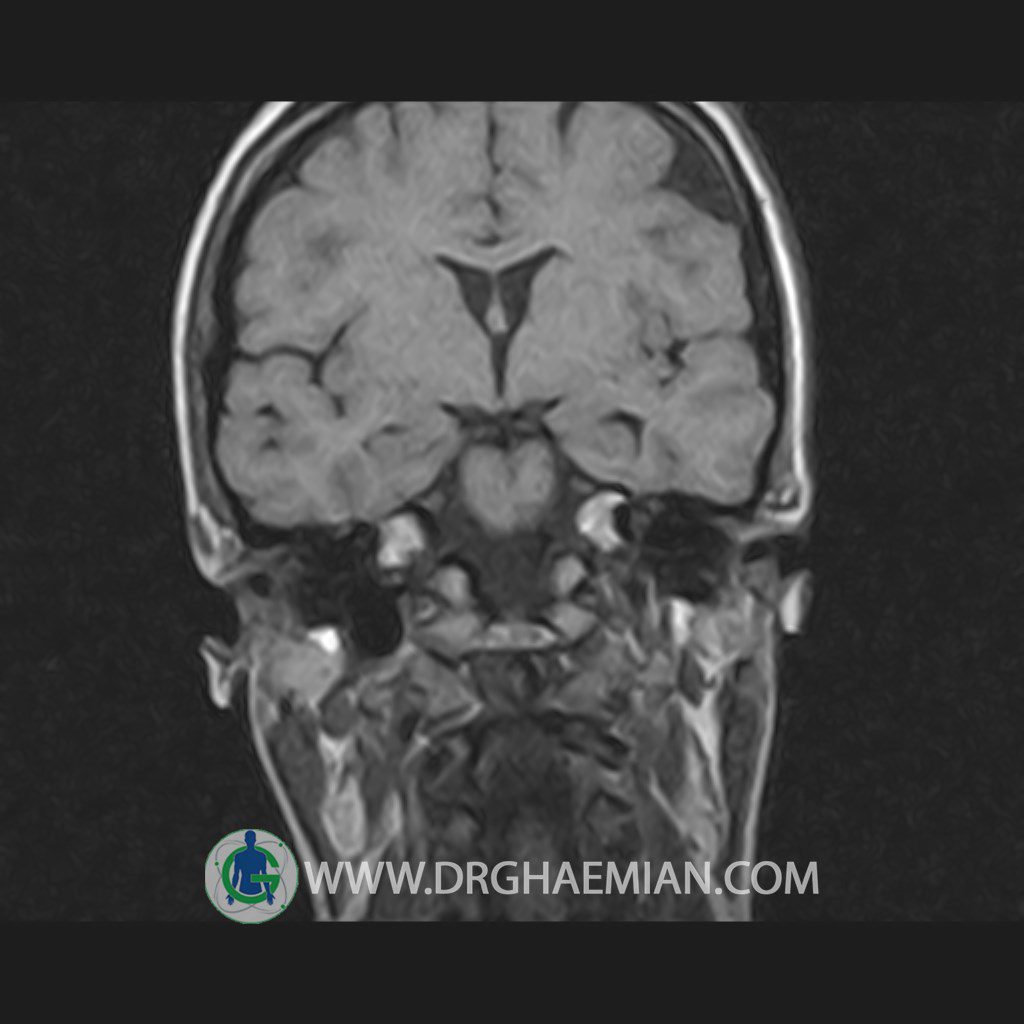

پزشکان اغلب از تصویربرداری ام آر آی برای تشخیص و درمان عارضه های پزشکی که فقط با استفاده از اشعه ایکس یا میدان مغناطیسی و امواج رادیویی قابل مشاهده است، استفاده می کنند. دستگاه ام آر آی تصاویر دقیق از ساختار های داخلی بدن ایجاد می کند. در این کیس هیپرپلازی هیپوفیز و آدنوم مشاهده می شود.

HYPOPHYSIS MRI

(with and without contrast)

Technique: Axial , coronal T1 , Axial , coronal , sagittal T2 , Axial, coronal T1 post Gd & 64 dynamic thin coronal slices.

REPORT :

The sella shows normal size , position and configuration .

The borders of its floor and walls are smooth and sharply defined .

The infundibulum is centered and of normal size .

The optic chiasm and suprasellar spaces appear normal .

The cavernous sinus and imaged portions of the internal carotid artery and carotid siphon are unremarkable .

Evaluable portions of the neurocranium show no abnormalities .

The sphenoid sinus is clear and pneumatized .

– Mild convexity at superior border of pituitary gland with post contrast homogeneous enhancement suggestive for pituitary hyperplasia & iso signal adenoma

is seen